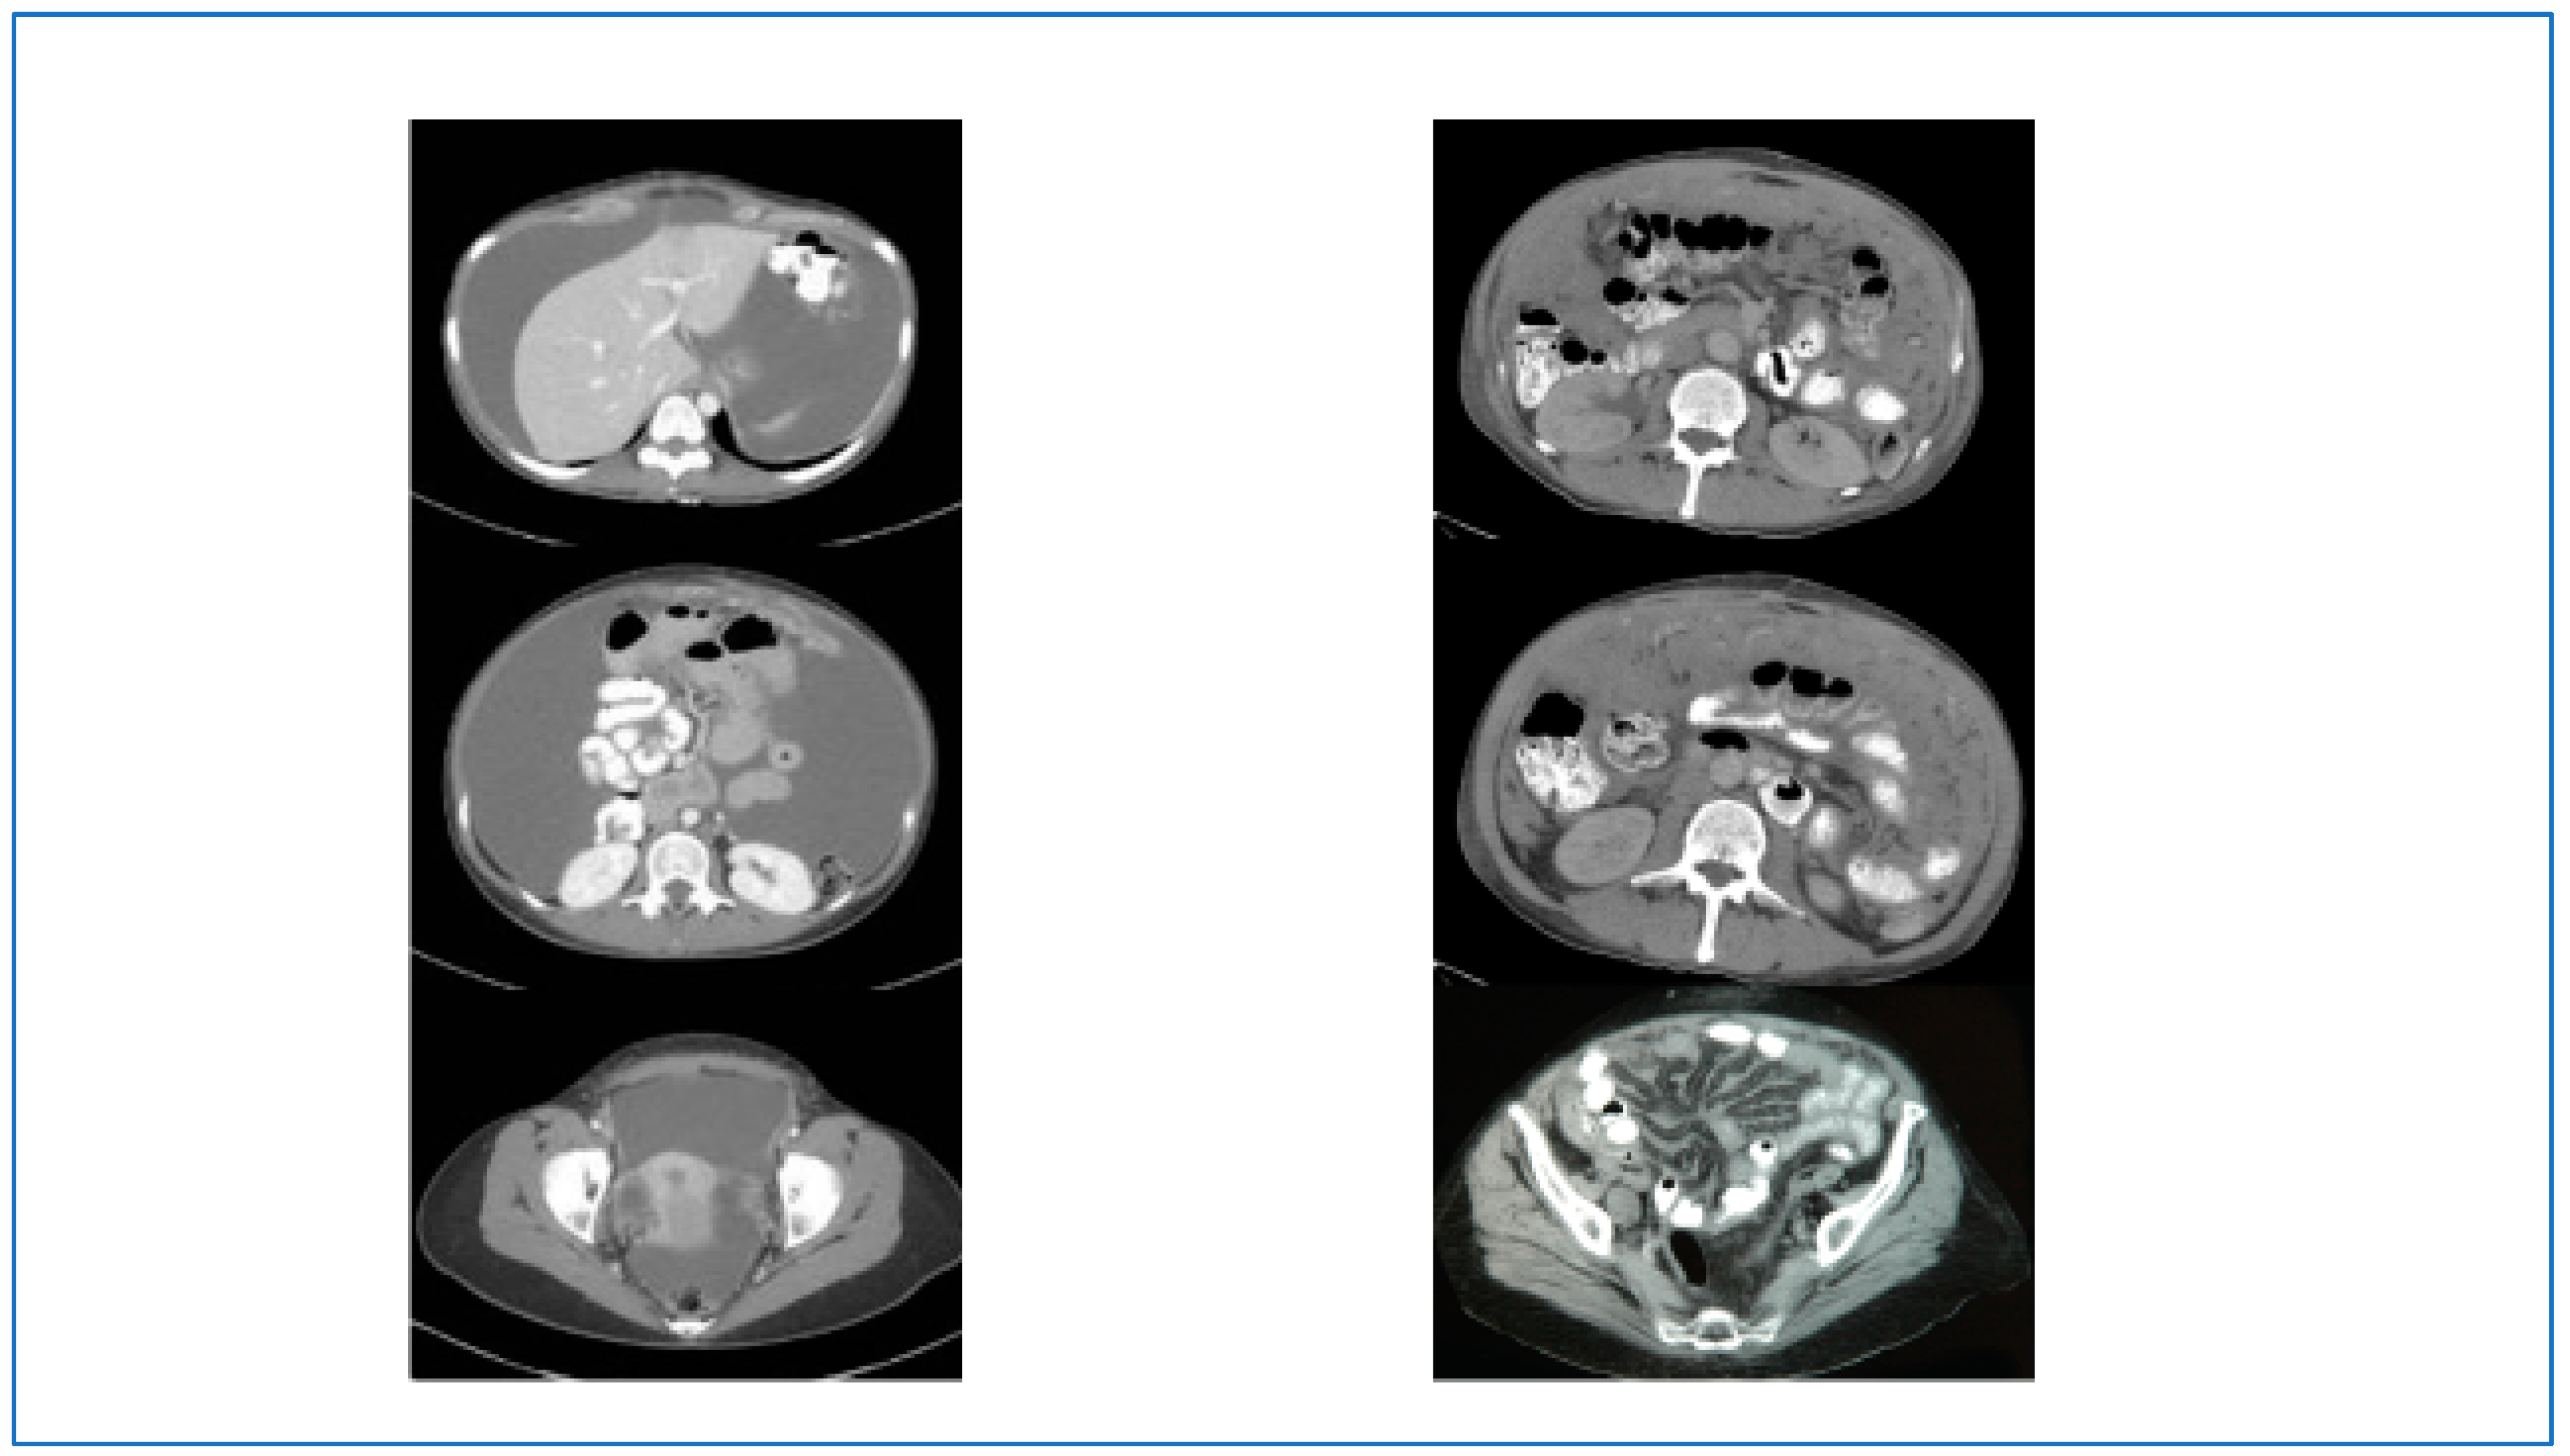

- Yan, T.D.; Haveric, N.; Carmignani, C.P.; Chang, D.; Sugarbaker, P.H. Abdominal computed tomography scans in the selection of patients with malignant peritoneal mesothelioma for comprehensive treatment with cytoreductive surgery and perioperative intraperitoneal chemotherapy. Cancer 2005, 103, 839–849. [Google Scholar] [CrossRef] [PubMed]